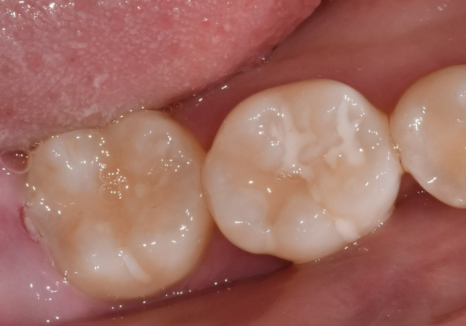

입안을 겉에서만 보았을 때는

사랑니(#48)가 머리만 살짝 보이고 있어서

큰 문제가 없어 보였죠.